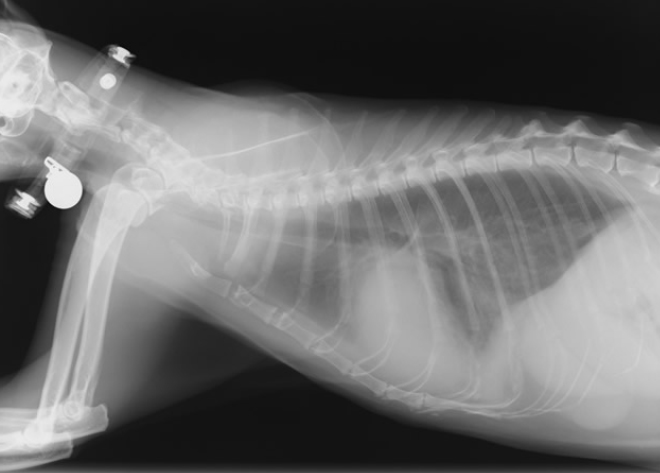

犬猫の先天性心疾患

動脈管開存症 (PDA:Patent Ductus Arteriosus)

胎子期に肺動脈と大動脈を繋ぐ動脈管が、出生後も残ってしまっている病気です。

左心室を出発した血流の一部が大動脈→動脈管→肺動脈→肺→左心系へと還流するため、左心系が常に血液量過多となります。

発見が早ければ、外科手術による完治が可能です。手術の方法としてコイル塞栓術、開胸下での血管結紮術の2種類があります。

正面像

側面像